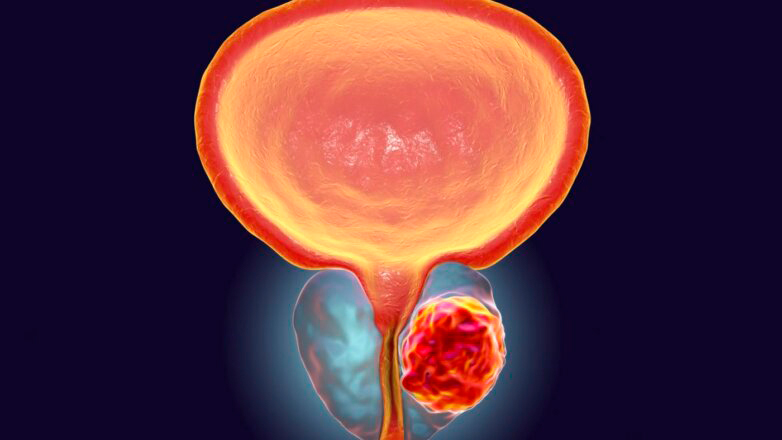

Kαλοήθης υπερπλασία του προστάτη: Σύγχρονη και οριστική λύση